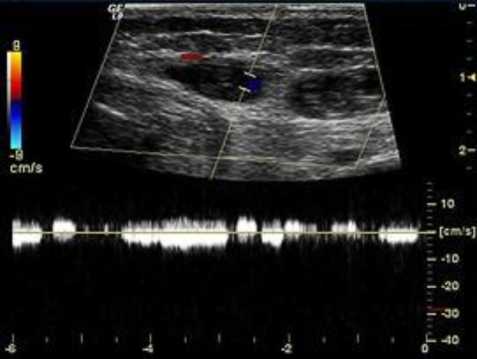

A program of complex preoperative examination included duplex scanning (DS) of vessels, ultraviolet scanning of soft tissues, and computed or magnetic resonance tomography (Figure 1). With these methods, the location and depth of the lesions and involvement of internal organs and adjacent anatomic structures were clarified.

Fig. 1. Duplex scanning of angiomatous tissues. Venous caverns with low-velocity blood flow based on the Doppler curve data

The study included patients with venous-cavernous forms of angiomatosis characterized by the existence of caverns, grapelike venous cavities separated with thin-walled trabeculas. According to their size, caverns were classified to small (5-20 mm), medium (21-30 mm), and large (>30 mm). The size of venous caverns in the analyzed clinical cases ranged from 5 to 32 mm, and the depth of the lesions ranged from 7 to 25 mm. Flebolytes were identified in 9 (45.2%) patients.